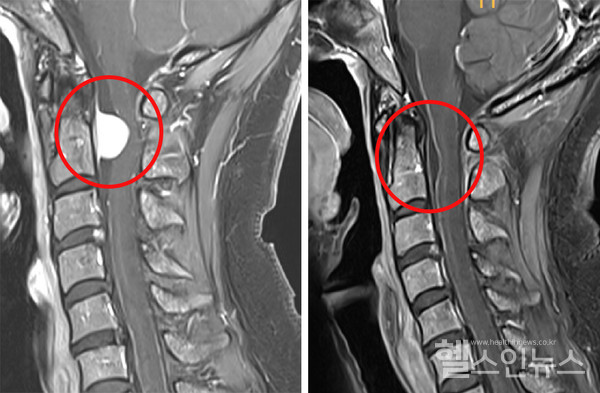

2020년 심한 어깨 통증과 물건을 이유 없이 떨어트리는 증상으로 병원을 찾은 환자 홍 씨(45세, 여성)는 MRI 검사 결과 ‘척수종양’ 진단을 받았다. 종교적 신념으로 수혈을 원치 않았던 홍 씨는 유명하다는 서울 유수의 대형병원과 대학병원 5곳에서 진료를 받았지만, ‘종양이 척수신경의 앞쪽 위치에 있어 마비의 위험이 크고, 출혈 위험이 있어 무수혈 수술은 어렵다’는 말을 공통적으로 들었다. 2년간 수술을 받지 못했고, 이제는 상지뿐 아니라 다리까지 약해져 걷기 힘든 증상도 나타났다. 홍 씨는 종교단체 교섭위원회를 통해 여러 교우가 ‘임수빈 교수에게 수술받고 호전됐다’는 이야기를 듣고 순천향대 부천병원을 찾았다. 임수빈 교수는 홍 씨의 종양을 수혈 없이 완전히 제거하는 데 성공했다.

임수빈 교수는 “종양이 뇌간과 척수의 이행부이자 신경구조의 앞쪽에 위치해, 보통의 방법인 뒤쪽 정중선 접근과 후궁 절제를 통한 수술은 전신마비의 위험이 크고 근육견인손상 및 출혈 위험도 있어서 다른 방법을 찾아야 했다”고 말했다. 이에 임수빈 교수는 귀 뒤쪽으로 접근해 척수를 둘러싼 경막의 옆에서 경막을 절개 후, 최대한 신경구조를 건드리지 않도록 수술 계획을 세웠다. 그 결과, 수술 시 수혈이 필요하지 않을 정도의 적은 출혈만 있었으며, 마비의 후유증도 없이 척수종양만 완전히 제거할 수 있었다.